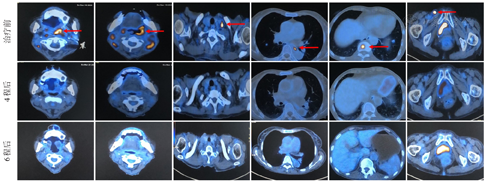

患者2020年12月31日开始予利妥昔单抗+来那度胺+泽布替尼+替雷珠单抗方案治疗1个周期,第1周期后第12天出现发热性粒细胞缺乏症,暂予停用泽布替尼,对症处理后恢复。继续原方案治疗4个疗程及6个疗程后PET-CT示原代谢增高部位均已不明显,Deauville评分3分,均评估为完全缓解(图1)。患者已完成6个疗程治疗方案,后续诊疗建议予泽布替尼+来那度胺+PD-1抗体维持1年,目前正在随访中。